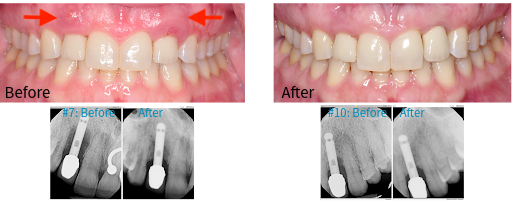

Comparison of dental before and after photos, showing improved implant health after LAPIP.

Laser Assisted Peri-implantitis Procedure

(To treat peri-implant disease)